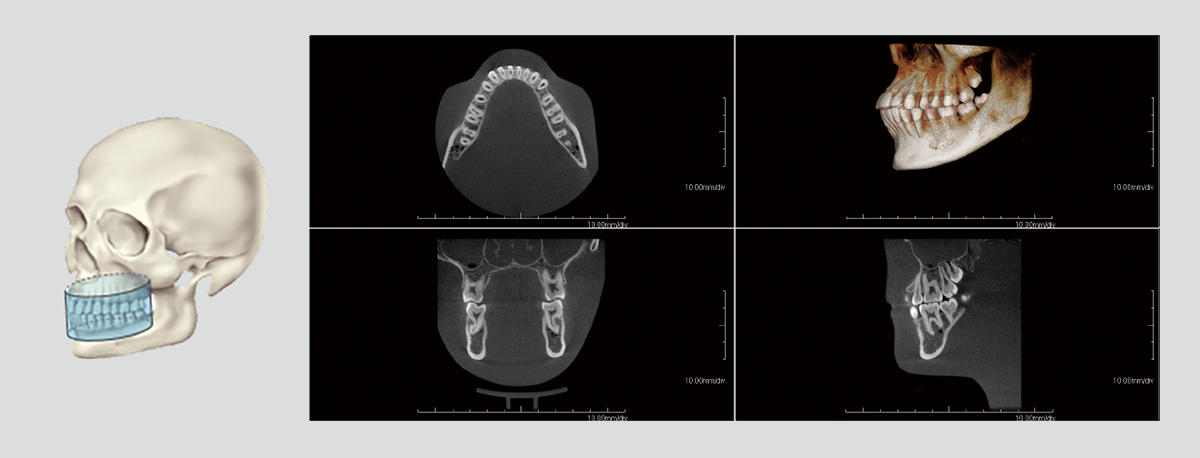

With dentists from various fields of expertise as advisors, we have carefully selected FOVs that are commonly used in clinical practice. In addition to the 3D analysis function for image detail sizes of 5x5cm, 10x10cm, 15x10cm and 15x16cm, the device features “True” and “Reconstructed” panoramic modes. With one of the largest FOVs on the market, the PreXion3D EXPLORER helps to develop the best therapy options, particularly in oral and maxillofacial surgery, airway analysis and orthodontics, as well as ear, nose and throat medicine. The use of a large 25.4x31.7cm FPD enables 15x16cm FOV scanning in one rotation.

The precise and high-resolution display of hard and soft tissue enables outstanding diagnostics and planning across all areas of modern dentistry and maxillofacial surgery. A large high-definition FPD allows all FOVs scanned in a single rotation without using stitching function.